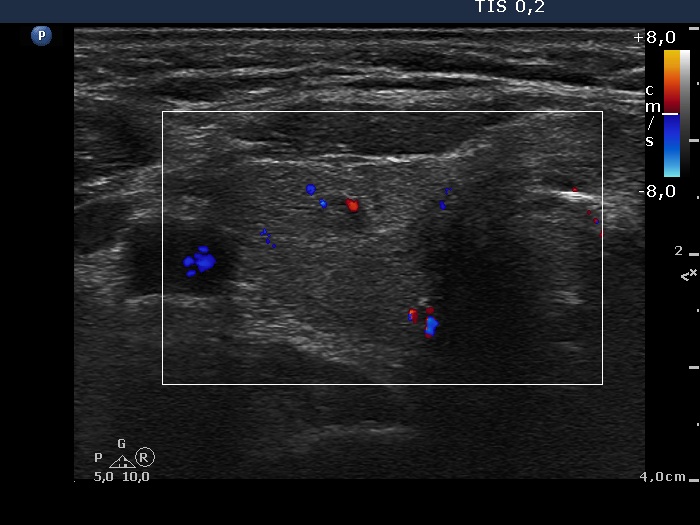

Right lobe, longitudinal scan

Right lobe, longitudinal scan, color Doppler method. The vascularization is not specific.